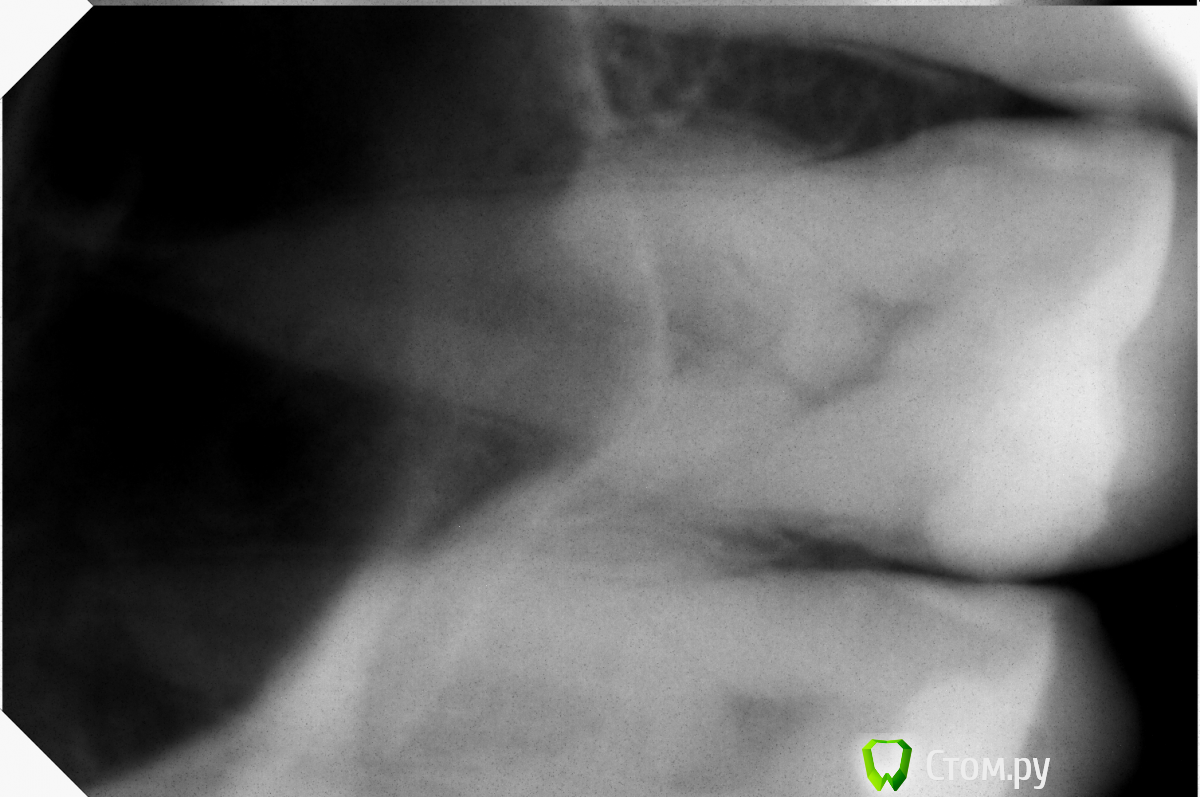

drkr8 Опубликовано 4 июня, 2014 Поделиться Опубликовано 4 июня, 2014 Здравствуйте, хотелось бы услышать оценку данным снимкам, потому что 4 разные клиники говорят разное. Ссылка на комментарий

IvanK Опубликовано 4 июня, 2014 Поделиться Опубликовано 4 июня, 2014 Кистой пугают? Ссылка на комментарий

drkr8 Опубликовано 4 июня, 2014 Автор Поделиться Опубликовано 4 июня, 2014 Кистой пугают? Все верно. Ссылка на комментарий

Гарриевич Опубликовано 5 июня, 2014 Поделиться Опубликовано 5 июня, 2014 Это гайморова пазуха ) 3 Ссылка на комментарий

drkr8 Опубликовано 5 июня, 2014 Автор Поделиться Опубликовано 5 июня, 2014 Хотелось бы услышать комментарий по поводу зуба. Стоматолог клиники сказал, что корни очень далеко идут, пломба очень массивная и давит на него, поэтому зуб нужно удалить. Ссылка на комментарий

faity Опубликовано 5 июня, 2014 Поделиться Опубликовано 5 июня, 2014 удалить всегда успеете, сделайте КТ. сколько полных лет, ещё вопрос? Ссылка на комментарий

faity Опубликовано 6 июня, 2014 Поделиться Опубликовано 6 июня, 2014 делайте КТ и лечите, потом коронку с вкладкой и никаких пломб Ссылка на комментарий